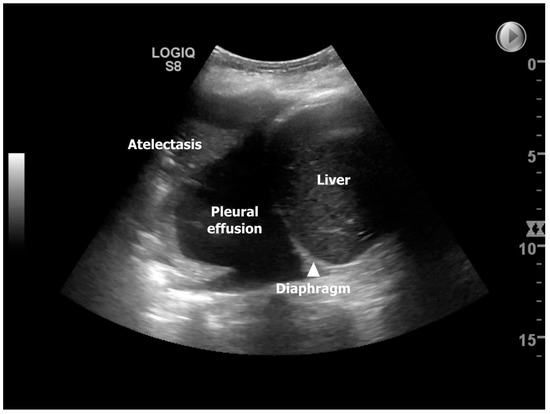

Figure 2.

Showing an ultrasound image in zone 3R on day 14. Ultrasonographic findings from a patient corresponding to post-transplant day 14 illustrating a moderate right-sided pleura effusion with concurrent compression atelectasis [11].

The use of TUS to discover the presence of many of the mentioned underlying conditions for developing ALAD has been explored in one national follow-up study from Denmark, where Davidsen et al. prospectively investigated 14 lung transplant recipients (13/1 double LTX (DLTx)/single LTx (SLTx)) at four time-points corresponding to post-LTx day 3 (TUS #1), 14 (TUS #2), 42 (TUS #3), and 84 (TUS #4) [11]. In this study, the most frequent pathological finding identified by TUS was pleural effusion, observed in 85.7%, 92.9%, 85.7%, and 78.6% of the lung transplant recipients equivalent to TUS#1-4, which may imitate a high prevalence throughout the entire 84-days observation period (Figure 2). However, in the study, the presence of pleural effusion was dichotomized, and as TUS can detect pleural effusion below 20 milliliters, this likely explained the findings that are consistent with an overall decreasing presentation over time, going from bilateral to unilateral and large/moderate to small pleural effusion. At TUS#2, the highest prevalence of compression atelectasis was found to be reliable, with the highest prevalence of pleural effusion. Pneumonia was most predominant at TUS#2 (28.6%), with decreasing prevalence at TUS#3-4 (14.3%), and during the observation period, neither lung transplant recipients were diagnosed with pulmonary embolism nor interstitial syndrome. Still, the most profound finding was that TUS as an add-on modality to ordinary LTx surveillance had a clinical impact in 10/14 lung transplant recipients (71.4%) during the observation period due to the detection of diagnoses with diverting interventions, such as re-operation due to sternotomy-related wound infection, pleural drainage, and initiation of/or changed antibiotic strategy. The prevalence of TUS-induced interventions was highest at post-transplant day 14 (TUS#2) and comprised half of the lung transplant recipients (n = 7 (50%)). The TUS observed findings from this study were assumed to be representative and compatible with the available knowledge on time-dependent pulmonary complications in the short-term post-LTx stages [26].